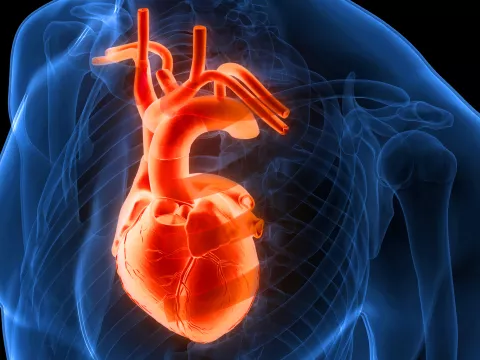

What exactly is atrial fibrillation (AFib)?

It’s an irregular heartbeat coming from the upper chambers of the heart (atria). In AFib, the atria will quiver and beat fast and cannot pump the blood effectively to the lower chambers of the heart — increasing the risk of stroke, heart failure and death.

What’s the difference between valvular and nonvalvular AFib?

AFib is considered valvular in people who have moderate or severe mitral valve stenosis or a prosthetic heart valve. Nonvalvular AFib generally is caused by other things, such as high blood pressure or stress.

What is the function of the left atrial appendage?

The left atrial appendage (LAA) is a small pouch in the left atrium that can act as a decompression chamber when atrial pressure is high. When patients develop AFib, they

experience poor atrial contractions which, combined with blood pooling, result in clot formation — mostly in the LAA.